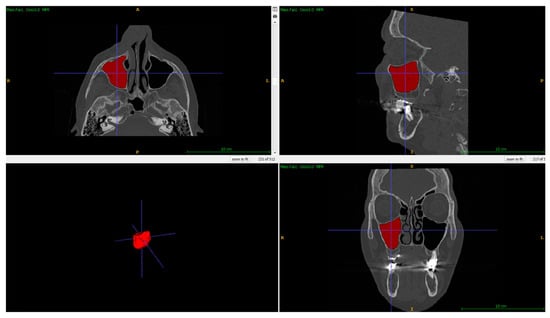

2. Materials and Methods